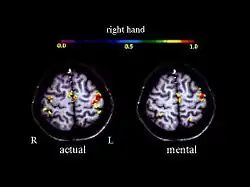

Activation in the motor cortex during motor imagery amounts about 30 % of the level observed during actual performance; Roth et al., 1996.

A large number of functional neuroimaging studies have demonstrated that motor imagery is associated with the specific activation of the neural circuits involved in the early stage of motor control (i.e., motor programming). This circuits includes the supplementary motor area, the primary motor cortex, the inferior parietal cortex, the basal ganglia, and the cerebellum.[21][22] Such physiological data gives strong support about common neural mechanisms of imagery and motor preparation.[23]